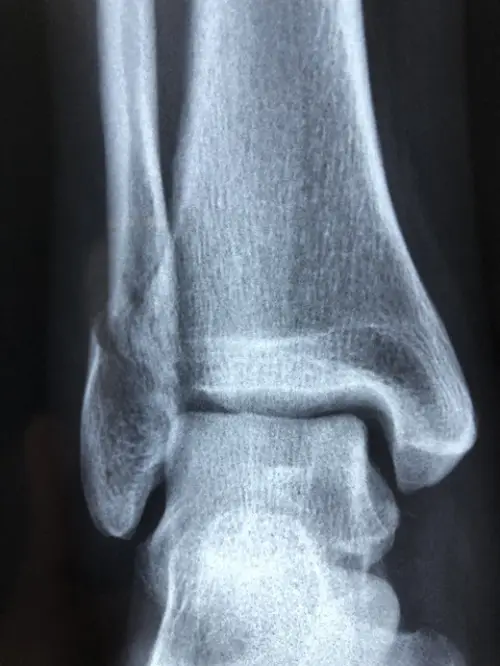

진단에서 영상검사는 필수적입니다. 가장 기본적으로 시행하는 X-ray 검사는 부주상골의 존재 여부, 크기, 형태 및 주상골과의 연결 상태를 확인할 수 있습니다. 특히 부주상골의 분류(1형, 2형, 3형 등)와 증상 발생 가능성을 파악하는 데 필수적입니다.

더 정확한 골조직의 손상이나 미세 골절이 의심될 경우, CT(컴퓨터단층촬영)을 통해 뼈의 세밀한 구조를 확인합니다. 이 검사는 골절 유무뿐 아니라 부주상골과 주변 뼈 사이의 관계를 보다 명확히 해줍니다.

부주상골과 관련된 연부 조직의 상태, 특히 후경골건의 염증이나 파열을 평가하려면 MRI(자기공명영상) 검사가 가장 적합합니다. 연부 조직 변화가 명확히 드러나 치료 방향 결정에 도움이 됩니다. 또한 다른 유사 질환과의 감별 진단에도 MRI는 매우 유용합니다.

| X-ray | 부주상골 존재 확인, 형태 분류 | 기본 영상검사 |

| CT | 미세 골절 및 뼈 구조 정밀 검사 | 필요 시 추가 검사 |

| MRI | 연부조직 염증 및 파열 검사 | 감별 진단에 중요 |